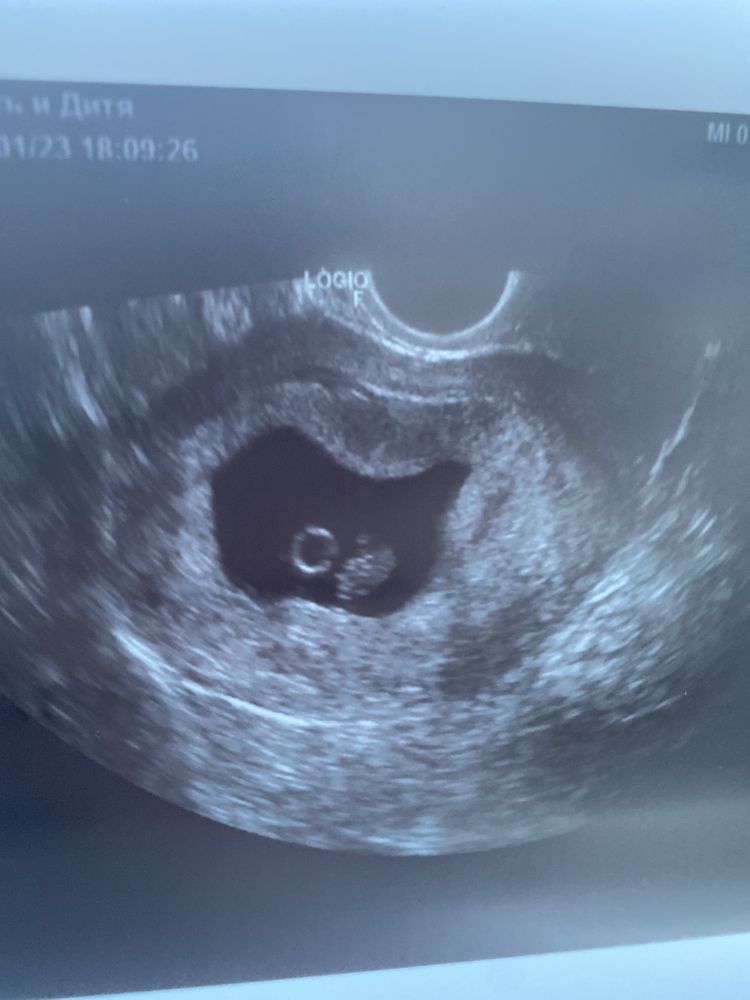

34дпп или 7 недель беременности

2 января делаю узи у своего ре- все отлично, бусинка растет, сердечко активно бьется, отслойки нет, активно начинает формироваться плацента)

Фотография человека имеется 😍